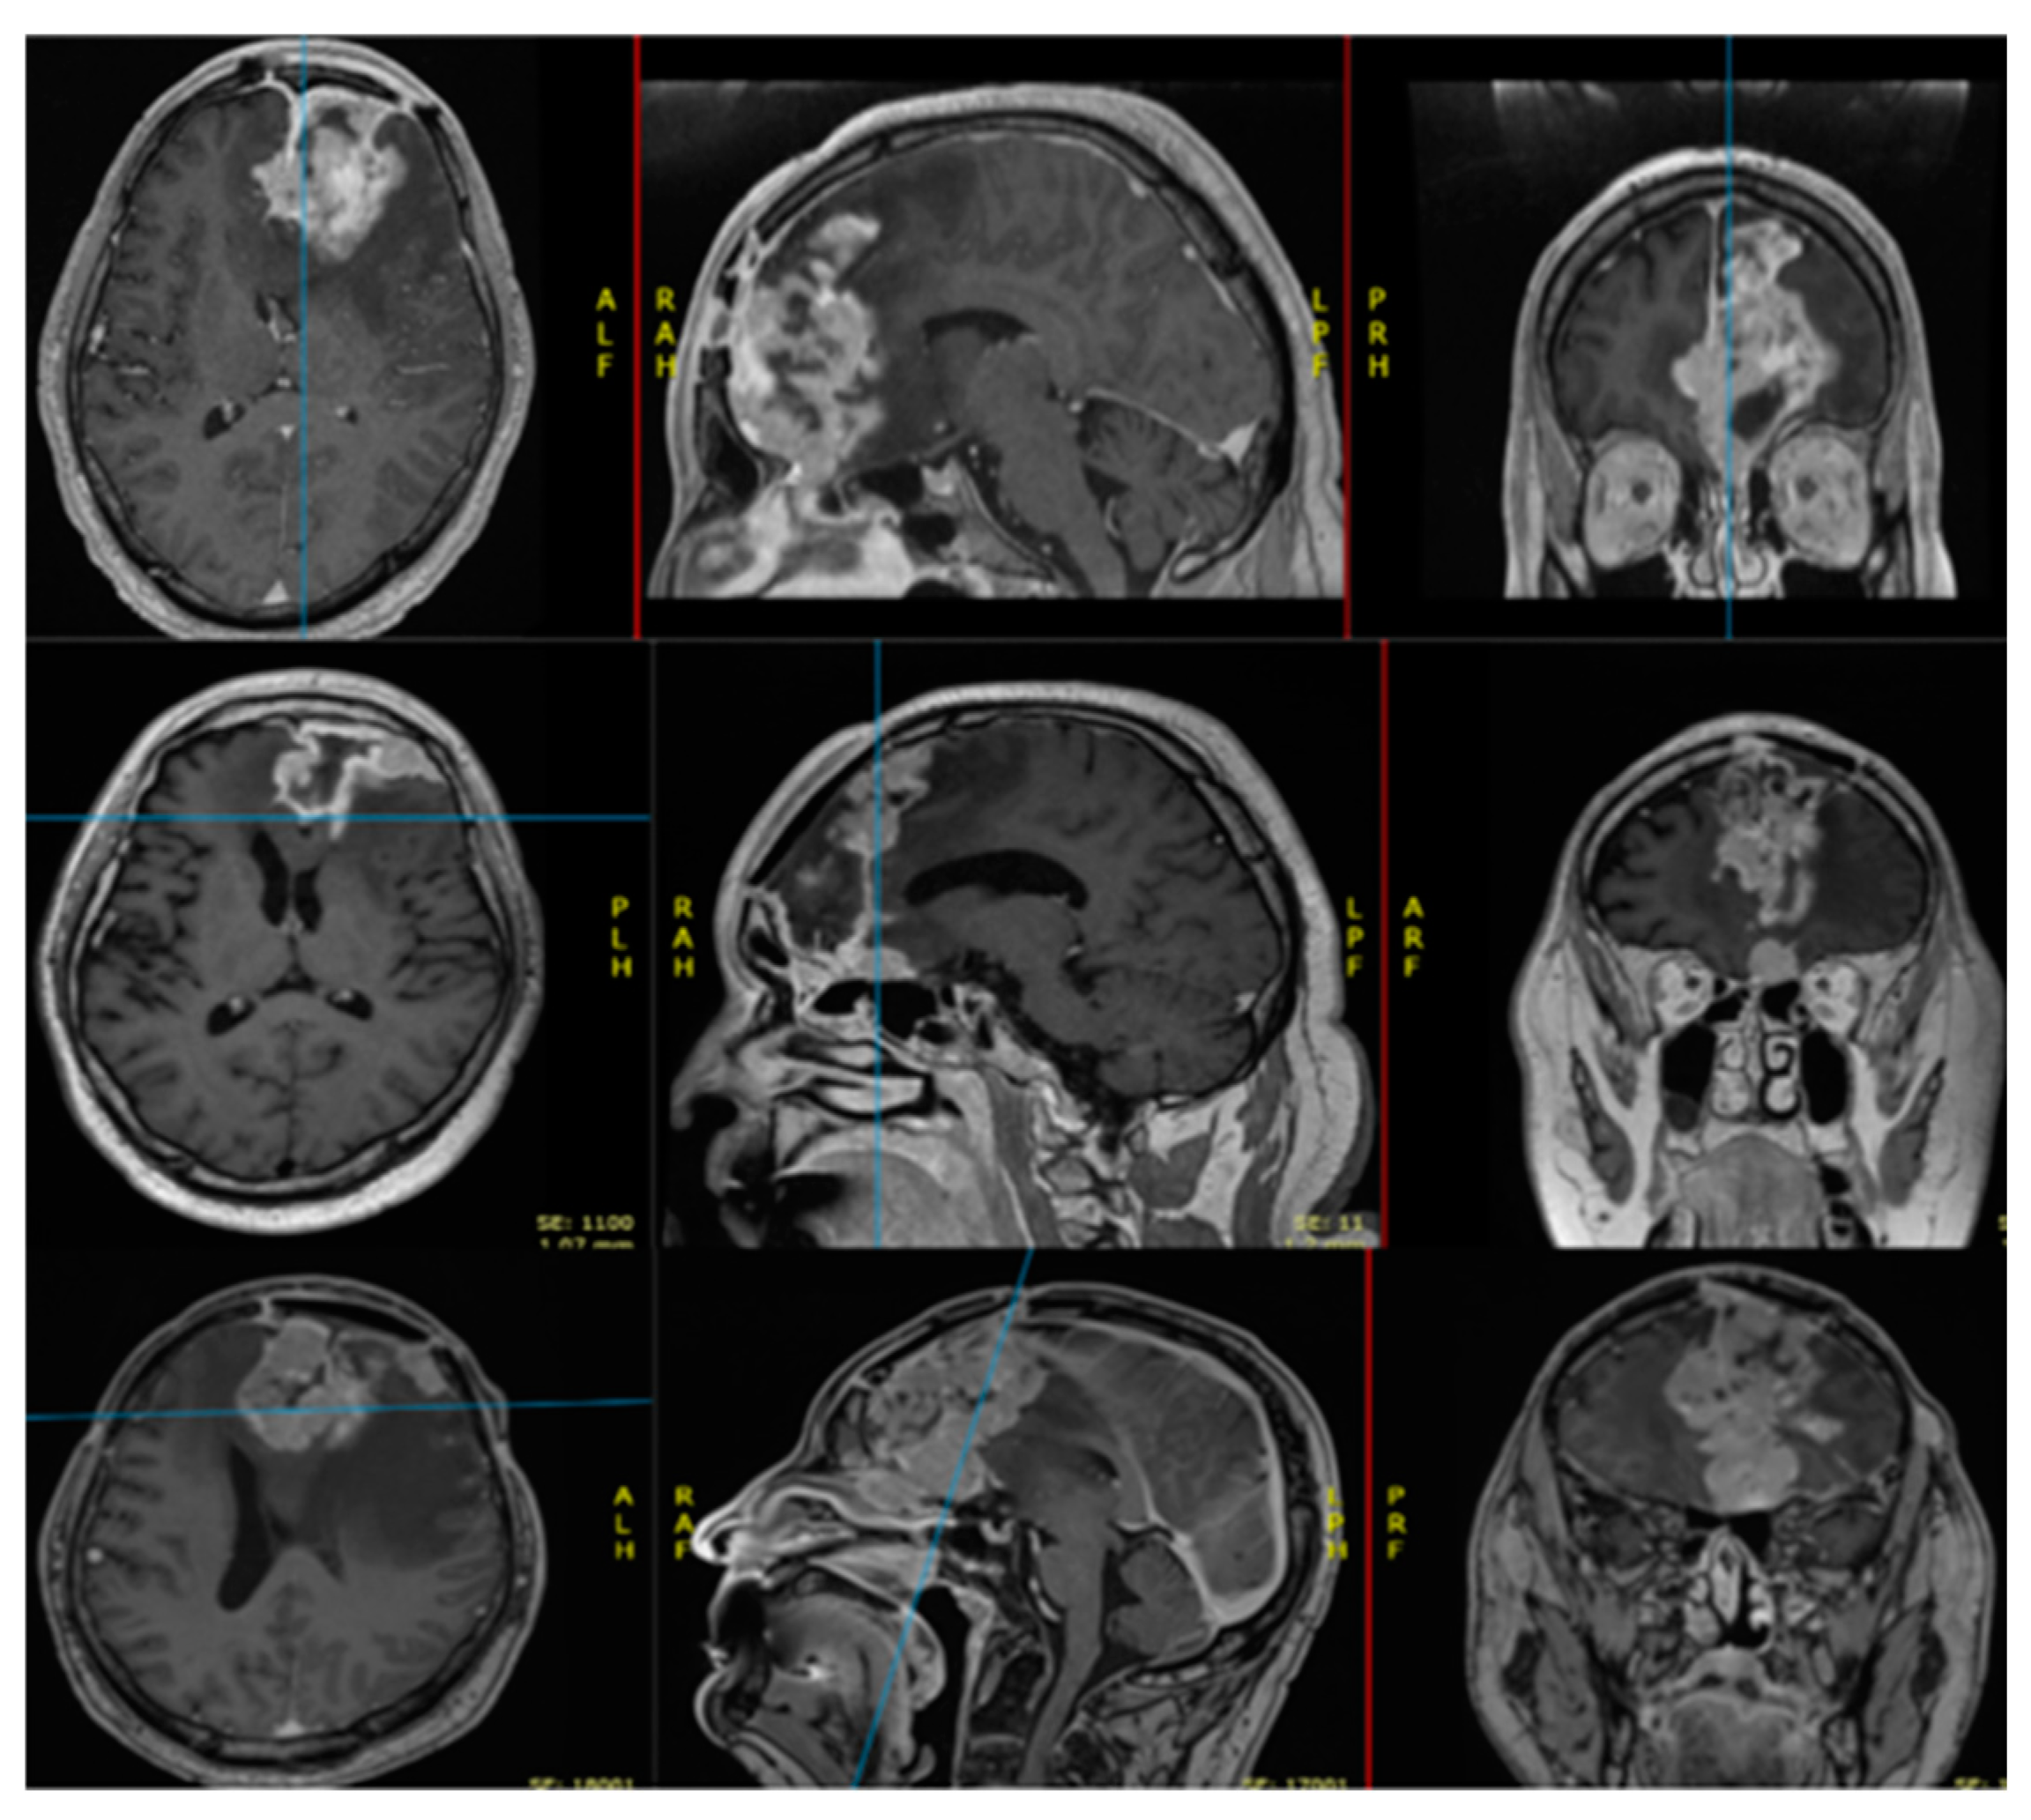

| CT/MRI Features of Grade 3 Meningiomas |

|---|

| Indistinct tumor–brain interface |

| Irregular tumor shape and margins |

| Heterogenous enchantment |

| Larger lesion |

| Absence of calcifications |

| Presence of perilesional edema |

| Volumetric growth rate |